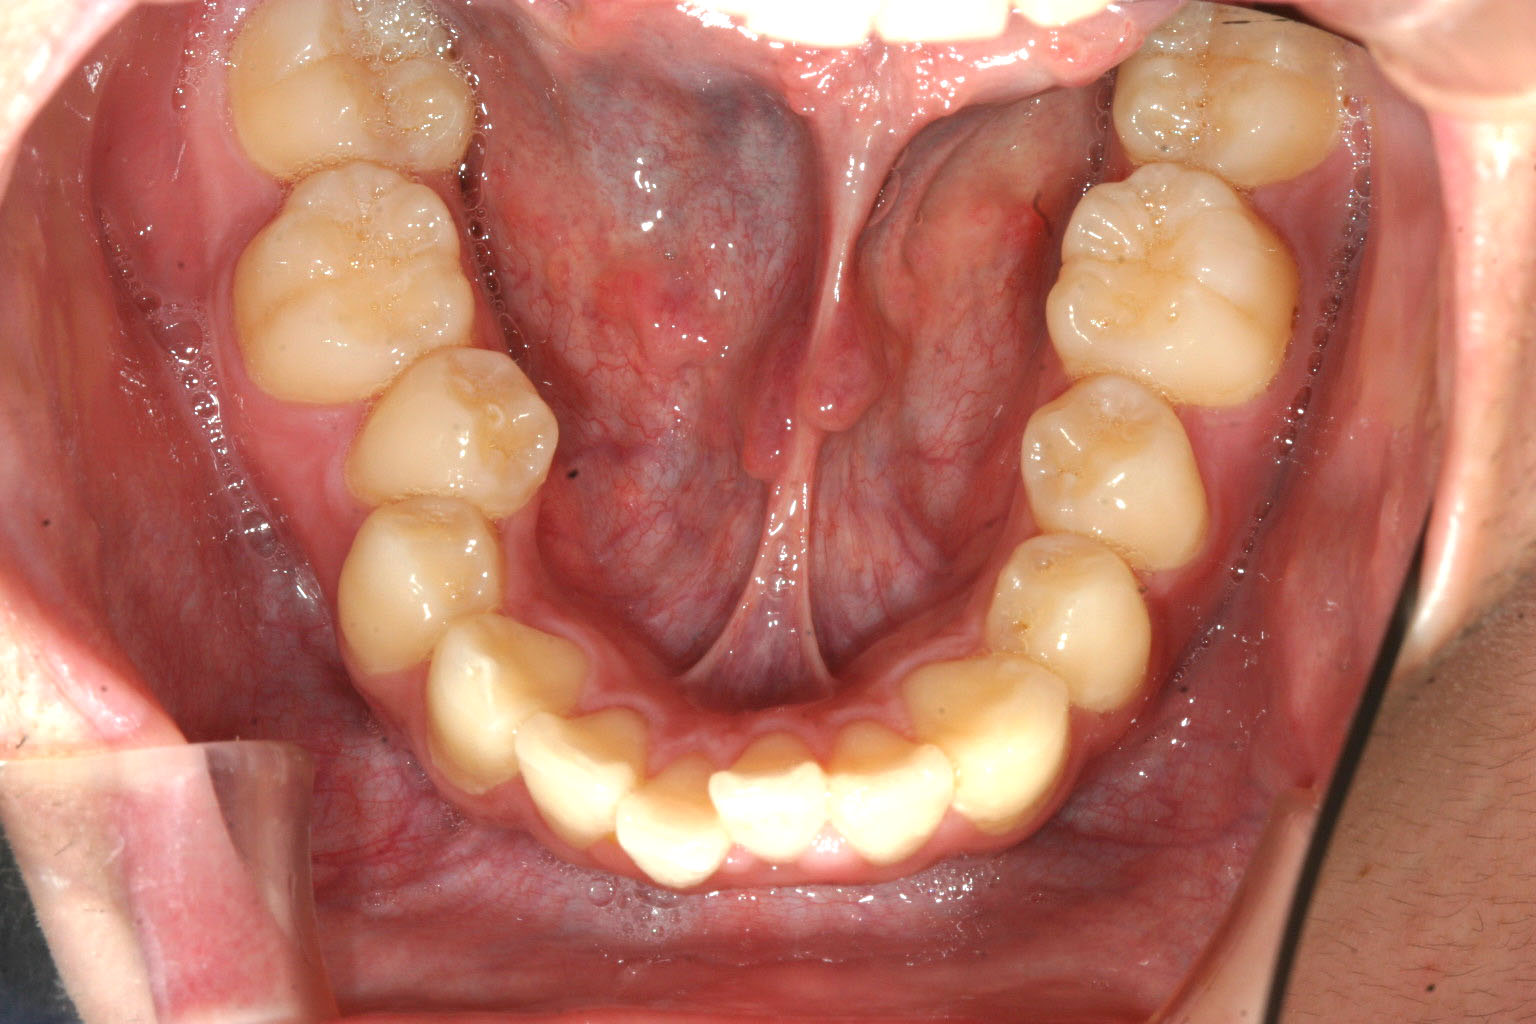

下顎も小臼歯部が狭くなり前歯が突出しています。

下顎も小臼歯部を広げました。